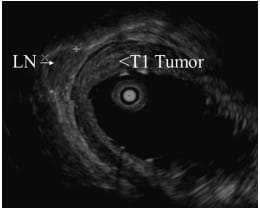

Early-Stage Cancer and Nodal Involvement

For early-stage esophageal and gastric cancers, EUS’s role primarily revolves around ruling out nodal involvement, a key factor in determining the disease’s progression.

EUS-guided FNA is instrumental in staging T1 or T2 esophageal and gastric cancers. Accurate determination of nodal involvement is critical in deciding between neoadjuvant chemoradiotherapy and direct surgical approaches.